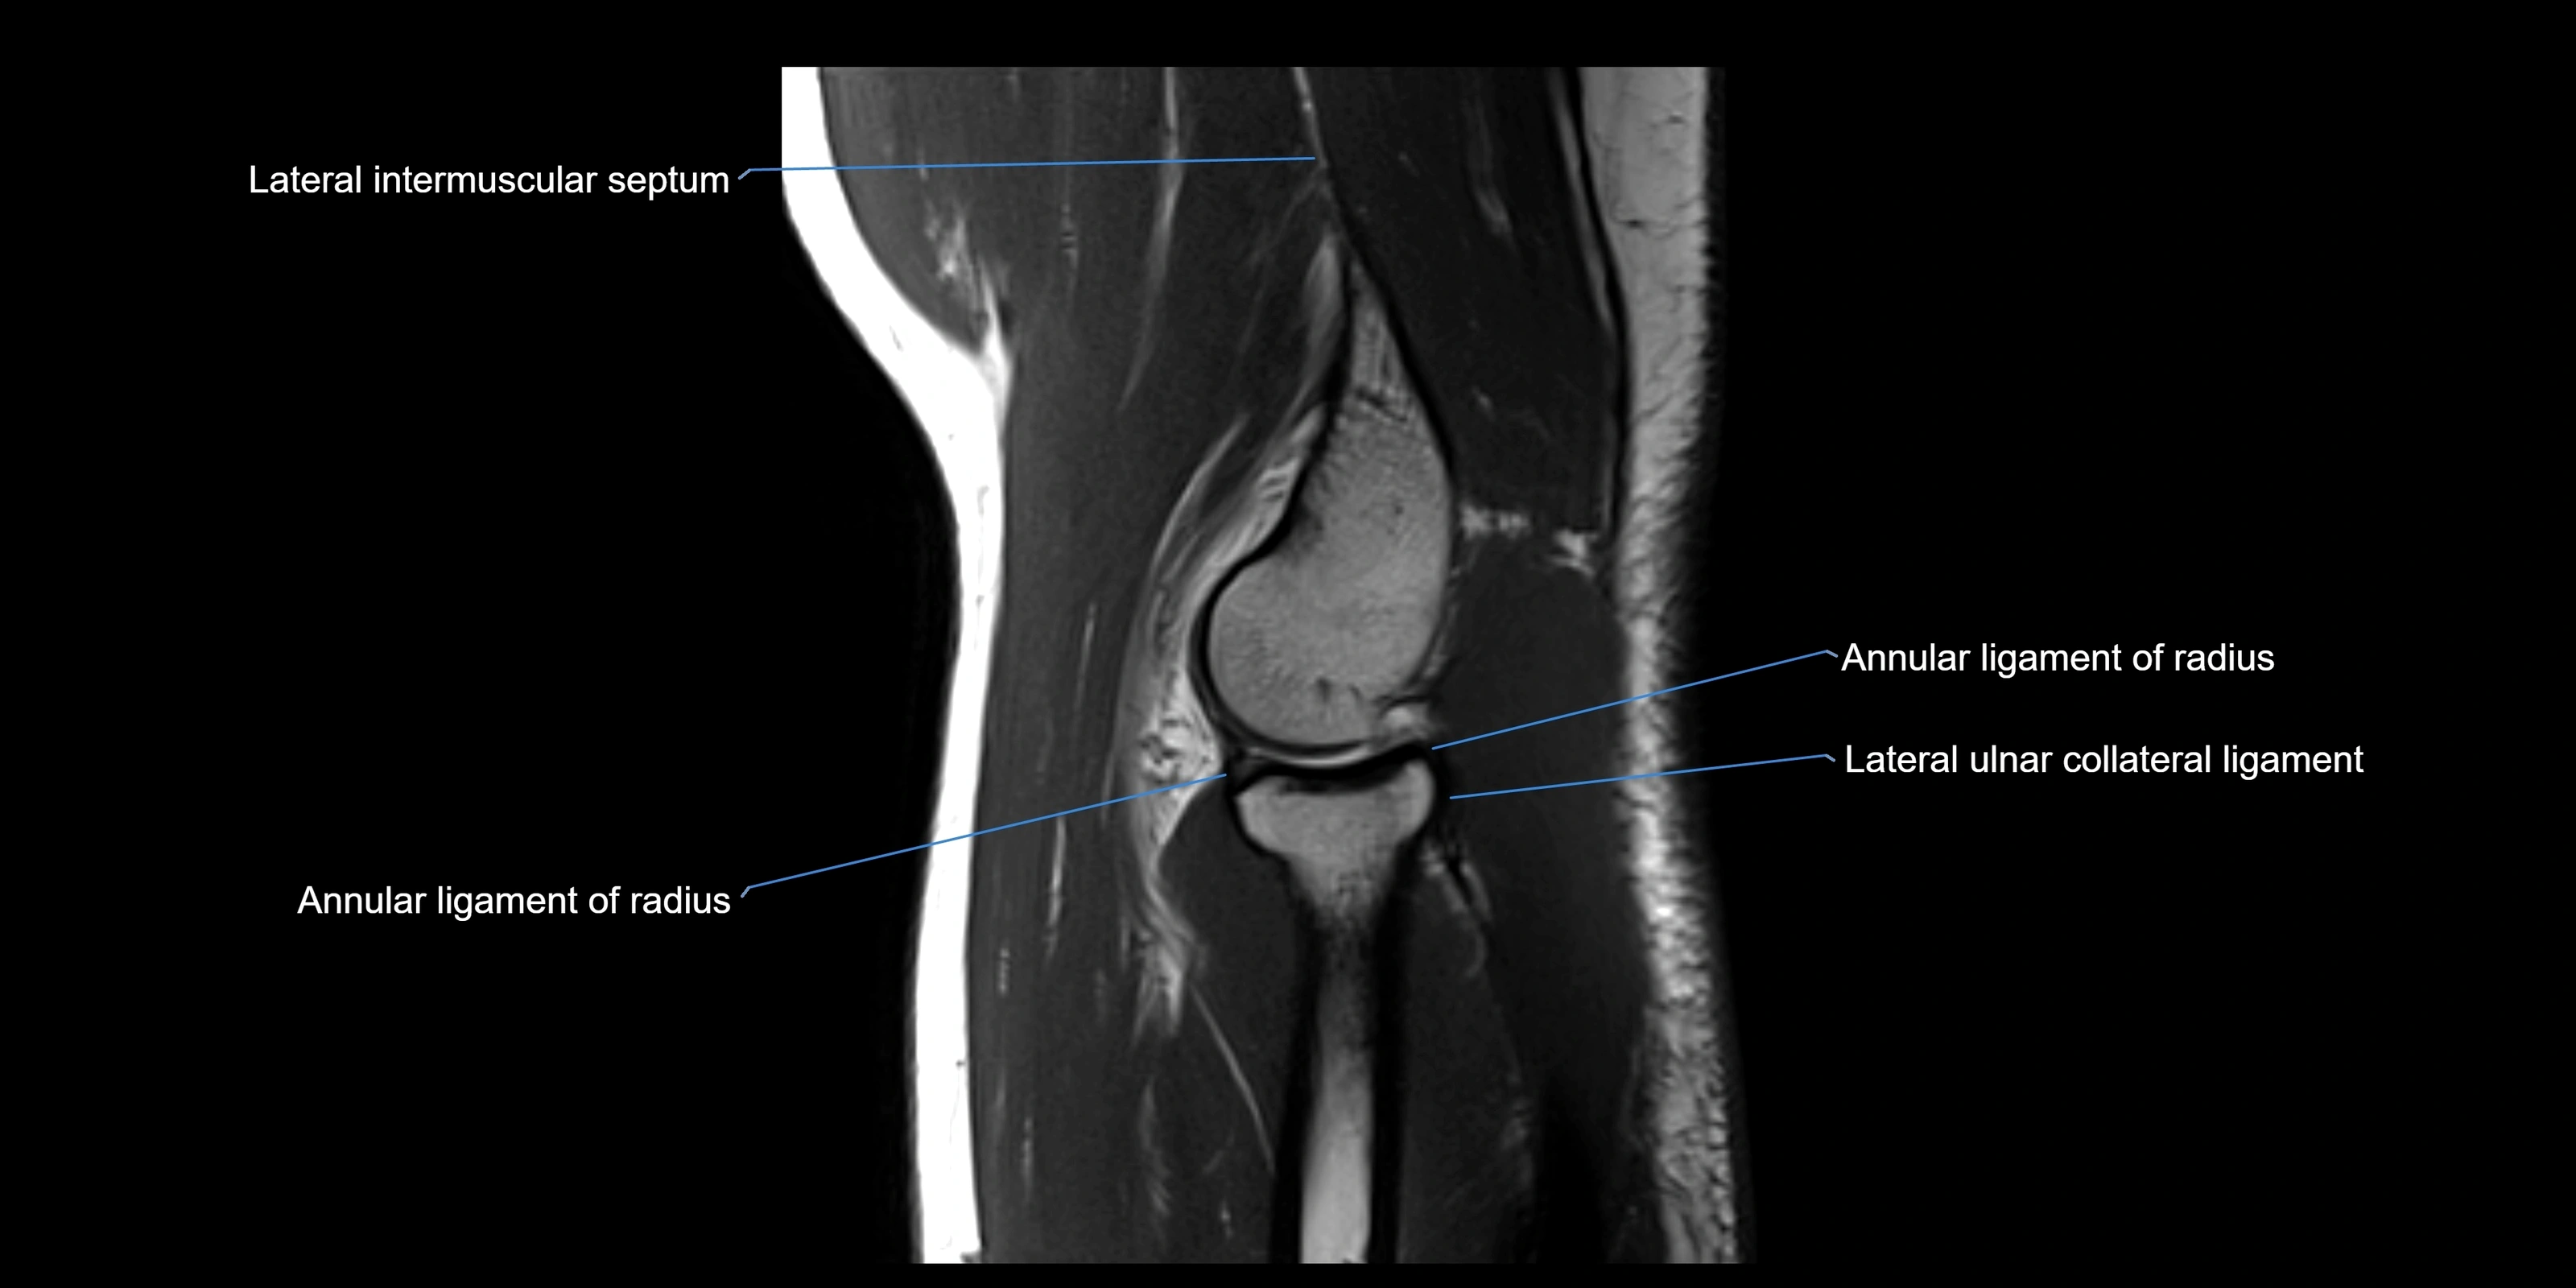

MRI images

image